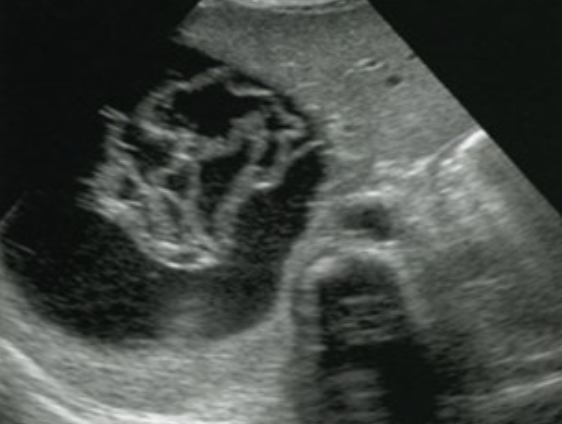

2D US: vascular involvement, large solid mass, distorts renal cortex, sinus, pyramids and contour, hydronephrosis, extension into renal vein, IVC, contralateral kidney, homogenous to complex, calcifications, well-defined

color doppler: hypovascular/vascular

DDX: neuroblastoma, hepatoblastoma

Nephroblastoma (Wilm’s Tumor) → 2nd most common peds abdominal cancer

clinical hx: 2-5 years, unilateral, Beckwidth-Wiedmann

s/sx: abdominal swelling, abdominal pain